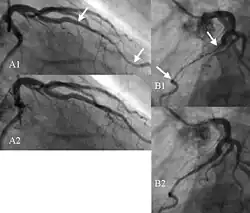

Angiogram showing myocardial bridging resulting in arterial compression.